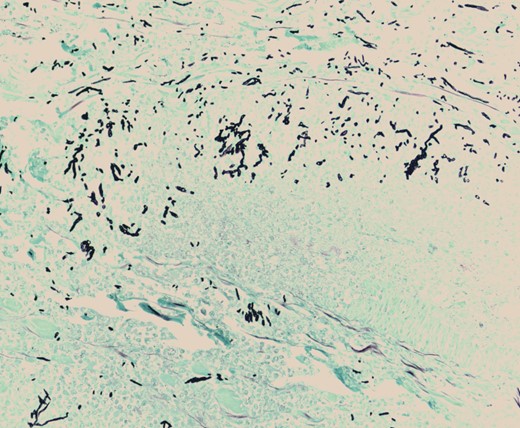

Pathologic evaluation of the resected bowel revealed hemorrhagic, gangrenous bowel (Fig. 1) and granular friable, ulcerated mucosa (Fig. 2). Microscopically, there were areas of transmural bowel necrosis (Fig. 3) and fungi within the bowel wall, artery wall and lumen (Fig. 4). Gomori Methenamine Silver stain was characteristic of Aspergillus species (Fig. 5).

Mononuclear cells associated with scattered neutrophils and prominent fungal hyphae in subserosal arteries and invading vessel walls.